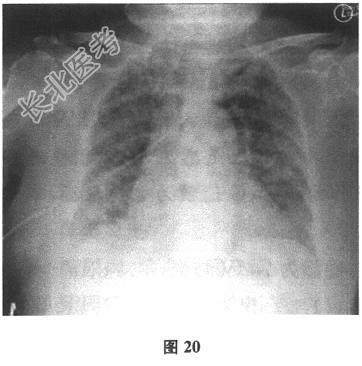

- [材料题] 患者男性,58岁。肾衰竭5年,肾移植术后2个月。因"发热、呼吸困难5天"入院。患者5天前无明显诱因出现发热,体温最高可达39℃,伴喘憋和畏寒,无明显寒战,偶有咳嗽,但无明显咳痰,有发热且感轻度头痛,无意识障碍,无胸痛,无咯血,未正规诊治,自服"退热药",仍反复发热。查体:体温38.8℃,脉搏110次/分,呼吸频率30次/分,血压130/90mmHg(1mmHg=0.133kPa),两肺呼吸音清晰,未闻及干湿啰音。血常规检查:白细胞计数5.8×109/L,中性粒细胞0.888,血红蛋白122g/L。未吸氧状态下动脉血氧分压50mmHg。胸部X线片:双肺见斑片状高密度影,右侧肋膈角模糊。

胸部CT:示双肺多发斑片、磨玻璃影,伴小叶间隔增厚和双侧少量胸腔积液(图20,图21)。